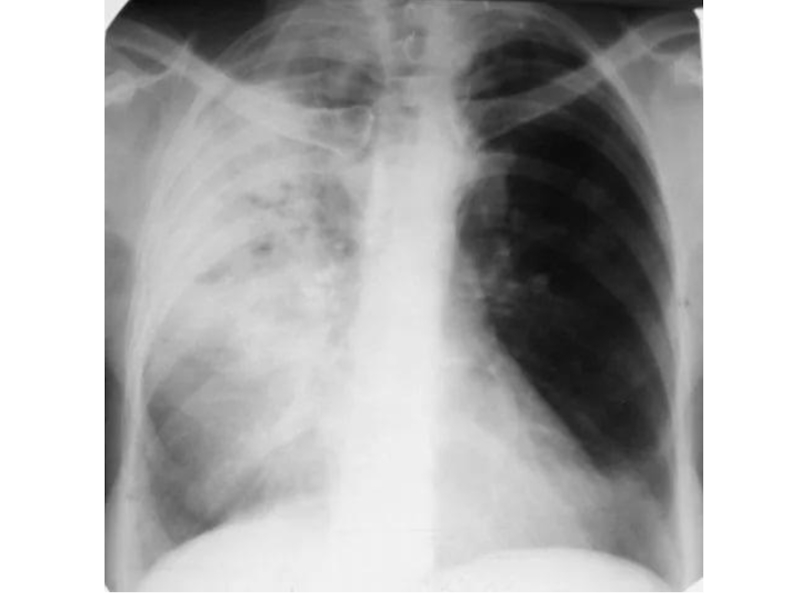

Крупозная пневмония (процесс захватывает целую долю, иногда все легкое, сопровождается воспалением

плевры):

На стадии прилива (первые 2-3 дня болезни альвеолы расширены и заполняются экссудатом) воздушность легочной ткани несколько снижена, легочный рисунок усилен, корень легкого расширен на стороне поражения.

На стадии опеченения (длится 3-5 дней, в альвеолах откладывается фибрин, в экссудат проникают клетки крови — сначала эритроциты, затем лейкоциты) воздушность резко снижена, корень легкого на стороне патологии расширен, прилежащая плевра утолщена, в плевральной полости может определяться экссудат. На снимке видна интенсивная тень в проекции одной или нескольких долей.

На стадии разрешения (наступает обычно к 7-10-му дню болезни) легочный рисунок усилен, корень легкого расширен, тень уменьшена и фрагментирована.

Обогащение легочного рисунка и расширение корня легкого сохраняется еще на протяжении месяца после исчезновения клинических проявлений.

а — красное опеченение; б — серое опеченение